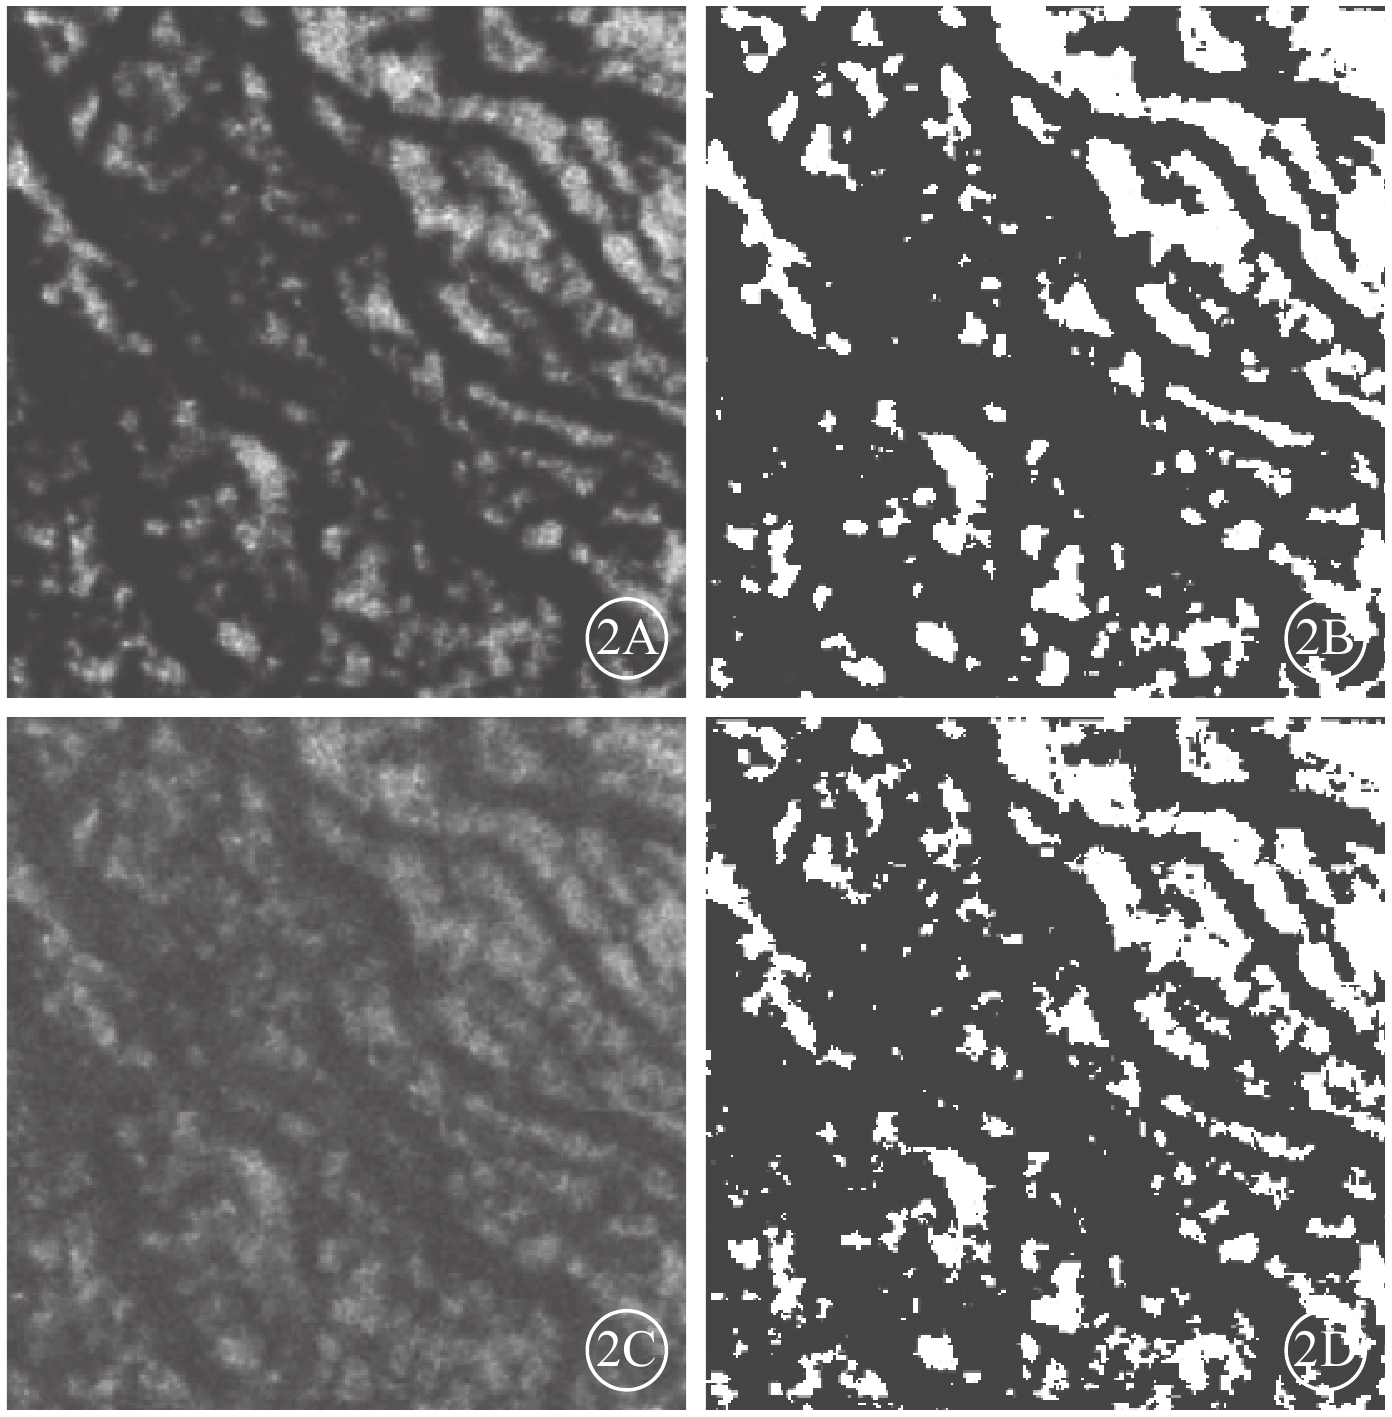

Bruch膜下1/2脈絡膜厚度層面,SS-OCTA圖像呈現與平面(en-face)OCT所示脈絡膜大血管分布較為一致的黑色血流信號,經二值化處理后所得的黑白圖像能反映脈絡膜大血管層的高速血流分布(圖2)。ECS組受檢眼脈絡膜SS-OCT和脈絡膜大血管層SS-OCTA表現為個別脈絡膜大血管極度擴張、高速血流匯聚和脈絡膜大血管普遍擴張、高速血流彌漫分布兩種類型。13只眼中,個別脈絡膜大血管極度擴張、高速血流匯聚6只眼;脈絡膜大血管普遍擴張、高速血流彌漫分布7只眼(圖3),其中1只眼為漿液性脈絡膜視網膜病變。對照組受檢眼脈絡膜SS-OCT無明顯大血管擴張征象,脈絡膜大血管層SS-OCTA圖像顯示高速血流分散而細小(圖4)。ECS組、對照組受檢眼脈絡膜大血管層FBFD分別為(76.35±14.46)%、(63.57±13.42)%;兩組受檢眼脈絡膜大血管層FBFD比較,差異有統計學意義(t=2.775,P=0.01)。

圖2

對照組黃斑區脈絡膜大血管層en-face SS-OCTA像及en-face OCT像。2A. SS-OCTA像;2B. 二值化處理后的SS-OCTA像;2C. en-face OCT像;2D. 二值化處理后的en-face OCT像。en-face SS-OCTA獲得的高速血流分布與en-face OCT獲得的血管分布具有較好的一致性

圖2

對照組黃斑區脈絡膜大血管層en-face SS-OCTA像及en-face OCT像。2A. SS-OCTA像;2B. 二值化處理后的SS-OCTA像;2C. en-face OCT像;2D. 二值化處理后的en-face OCT像。en-face SS-OCTA獲得的高速血流分布與en-face OCT獲得的血管分布具有較好的一致性

Bruch膜下1/2脈絡膜厚度層面,SS-OCTA圖像呈現與平面(en-face)OCT所示脈絡膜大血管分布較為一致的黑色血流信號,經二值化處理后所得的黑白圖像能反映脈絡膜大血管層的高速血流分布(圖2)。ECS組受檢眼脈絡膜SS-OCT和脈絡膜大血管層SS-OCTA表現為個別脈絡膜大血管極度擴張、高速血流匯聚和脈絡膜大血管普遍擴張、高速血流彌漫分布兩種類型。13只眼中,個別脈絡膜大血管極度擴張、高速血流匯聚6只眼;脈絡膜大血管普遍擴張、高速血流彌漫分布7只眼(圖3),其中1只眼為漿液性脈絡膜視網膜病變。對照組受檢眼脈絡膜SS-OCT無明顯大血管擴張征象,脈絡膜大血管層SS-OCTA圖像顯示高速血流分散而細小(圖4)。ECS組、對照組受檢眼脈絡膜大血管層FBFD分別為(76.35±14.46)%、(63.57±13.42)%;兩組受檢眼脈絡膜大血管層FBFD比較,差異有統計學意義(t=2.775,P=0.01)。

圖2

對照組黃斑區脈絡膜大血管層en-face SS-OCTA像及en-face OCT像。2A. SS-OCTA像;2B. 二值化處理后的SS-OCTA像;2C. en-face OCT像;2D. 二值化處理后的en-face OCT像。en-face SS-OCTA獲得的高速血流分布與en-face OCT獲得的血管分布具有較好的一致性

圖2

對照組黃斑區脈絡膜大血管層en-face SS-OCTA像及en-face OCT像。2A. SS-OCTA像;2B. 二值化處理后的SS-OCTA像;2C. en-face OCT像;2D. 二值化處理后的en-face OCT像。en-face SS-OCTA獲得的高速血流分布與en-face OCT獲得的血管分布具有較好的一致性